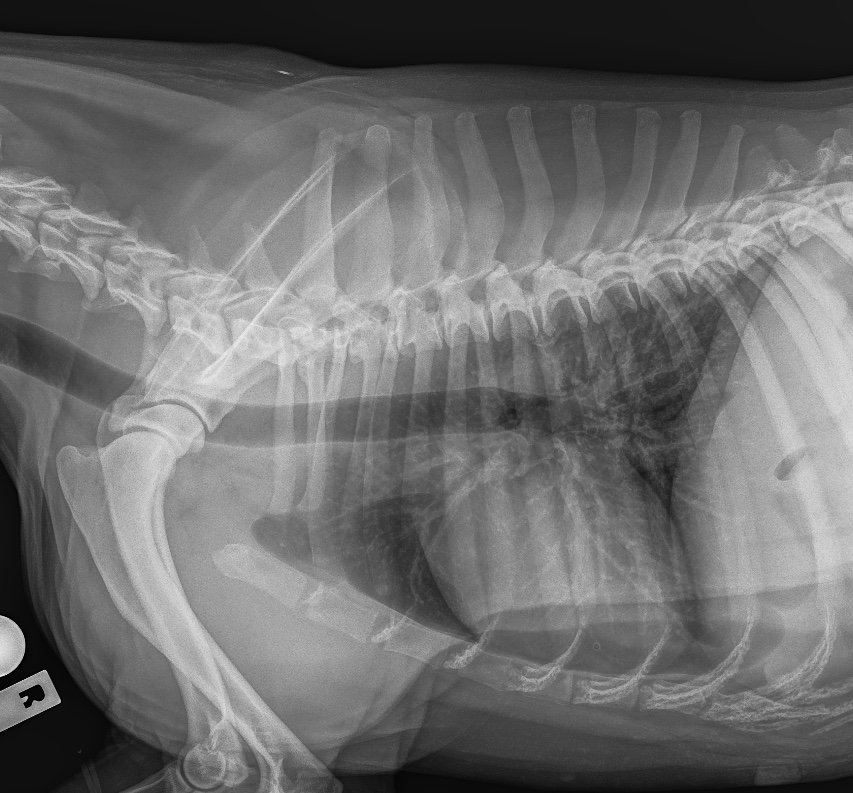

The Whyalla Veterinary Clinic has a new Shimadzu MUX10 Xray machine for high quality radiographs and a new Agfa XD14 Csi Tethered panel to produce outstanding direct digital Xrays from the images from the Shimadzu MUX10 Xray machine.

The XD14 CsI Tethered Panel is an integral part of an Agfa HealthCare’s Instant DR solution, which includes the NX image acquisition software with MUSICA3 processing and detector. These cassette-less and filmless solutions provide a range of workflow benefits that improve quality, productivity and speed up exam time.